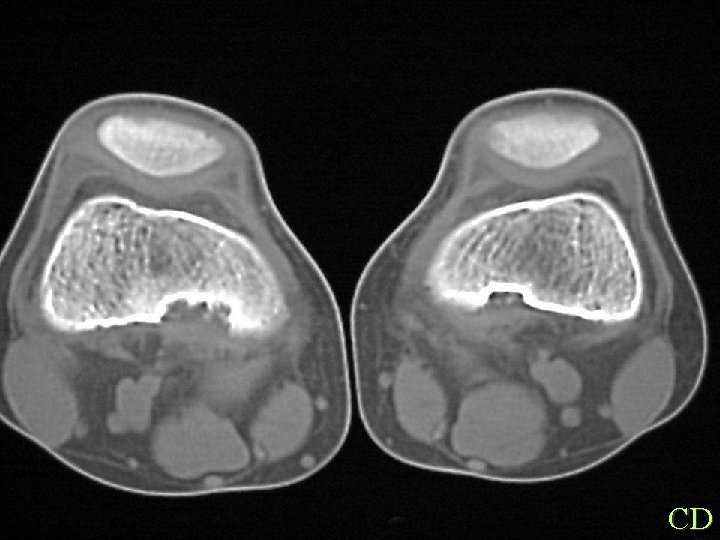

CD